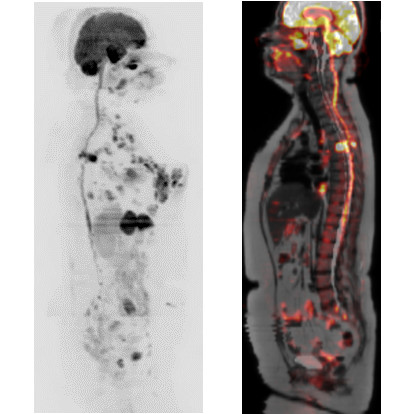

症例1:左乳癌術後経過観察(60代女性)

PET/CTではFDGの生理的集積のある膀胱も描出されている。

DWIBSでは正常な膀胱は描出されず、膀胱内や膀胱周囲の病変検出が可能。